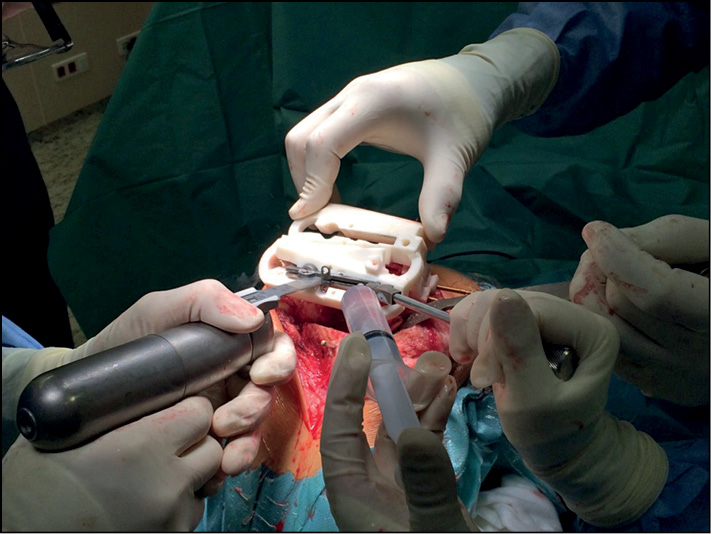

Во время выполнения хирургического лечения, после поднадкостничного выделения мыщелков бедренной и большеберцовой костей, устанавливается первый индивидуальный резекционный блок. Внутренняя поверхность индивидуального резекционного блока полностью повторяет костно-хрящевые анатомические особенности больного, что исключает смещение и погрешности при его фиксации к мыщелку бедренной кости. После фиксации пинами индивидуального резекционного блока в первую прорезь устанавливается запатентованный инструмент — направитель лезвия пилы — и выполняется первый дистальный опил (рис. 2).

Рис. 2. Выполнение дистального опила мыщелков бедренной кости.

Fig. 2. Performing a distal cut of the femoral condyles.